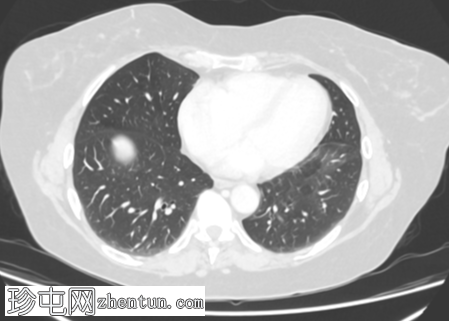

轴位

6.png

右肾中极前缘可见10毫米Bosniak II型囊肿,双侧肾盂旁可见囊肿。右肾下极可见两处肾皮质缺损。肝脏第8段可见5毫米囊肿。未见远处转移。L2椎体可见血管瘤。